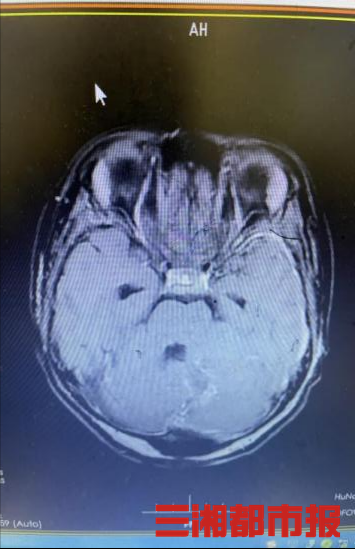

11月底,张先生的9岁女儿慕慕(化名)突然出现头痛、恶心、走路不稳等症状。连日来,这样的症状还不断加重,当地医院头部磁共振检查显示小脑蚓部占位性病变,考虑恶性髓母细胞瘤。

该科室杨杰教授及团队立刻给慕慕安排住院及术前检查,并给其父母下达了病危通知书,同时告知患儿父母亲相关手术事宜及风险。患者父母心情忐忑,商议后坚持手术治疗。杨杰教授率领医护团队,连夜加班讨论、分析病情,为其制定细致的手术方案及术后措施,决定于次日急诊行开颅探查+小脑蚓部占位性病变切除术。

随后,由主任医师杨杰主刀,副主任医师陈帅、章凯协助,手术团队成功为患儿实施开颅手术,完整切除肿瘤。从接诊到手术完成,医护团队历经24小时,成功将患儿从生死边缘拉了回来。

杨杰教授介绍,该患儿的术中快速病理显示为小脑蚓部恶性肿瘤,后续还应尽早进行基因检测,接受放化疗。